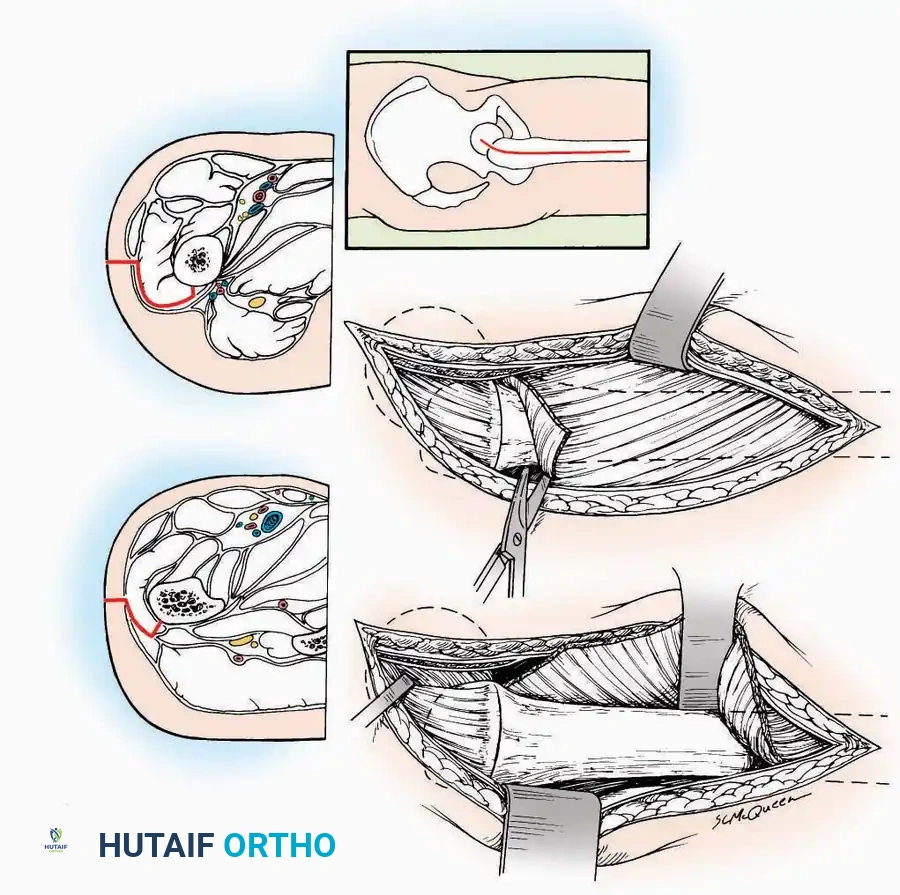

Anterior Approach

Indications: Total ankle arthroplasty (TAA), anterior ankle arthrodesis, and excision of anterior tibial/talar osteophytes (anterior impingement).

💡 Clinical Pearl

Gaining access to the medial gutter (the articulation between the medial malleolus and the medial articular facet of the talus) can be challenging through a pure anterior approach. Meticulous medial subperiosteal dissection of the joint capsule is required to avoid excessive traction on the anterior neurovascular bundle.

Surgical Technique:

* Incision: Make a 10 to 15 cm longitudinal incision over the anterior aspect of the ankle, centered exactly midway between the medial and lateral malleoli.

* Superficial Dissection: Incise the superficial fascia. Identify and protect the superficial peroneal nerve branches laterally and the saphenous nerve medially.

* Internervous Plane: The deep dissection exploits the plane between the Extensor Hallucis Longus (EHL) tendon (innervated by the deep peroneal nerve) and the Extensor Digitorum Longus (EDL) tendons (also innervated by the deep peroneal nerve).

* Neurovascular Bundle: Incise the extensor retinaculum. Carefully identify the anterior tibial artery and the deep peroneal nerve, which typically lie between the EHL and EDL, or directly deep to the EHL. Retract the neurovascular bundle laterally with the EDL, or medially with the EHL, depending on the specific anatomical variant encountered (lateral retraction is most common).

* Capsulotomy: Incise the anterior joint capsule longitudinally. Elevate the capsule subperiosteally from the anterior tibia and the talar neck to expose the entire tibiotalar articulation.